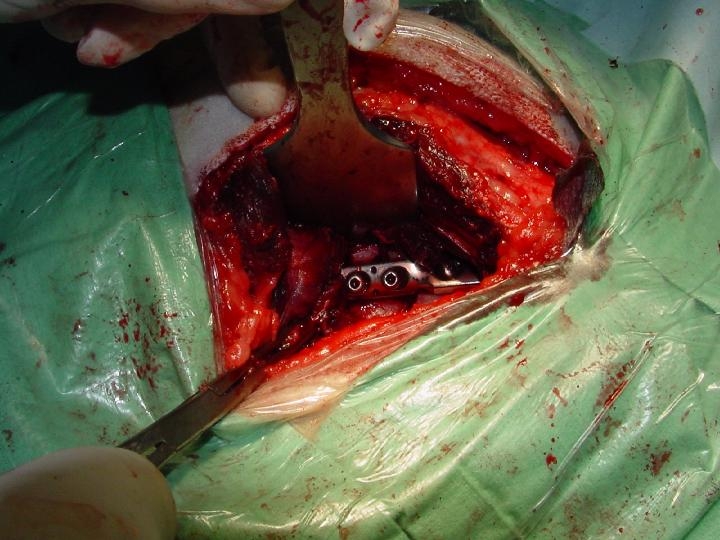

- Osteotomia do Ilium

Abordagem lateral do ilium. Os músculos glúteos são reclinados. Colocam-se os retractores de Hohman no bordo dorsal do corpo do ilium com a dupla finalidade de separar os músculos glúteos e obter uma melhor visão da zona.

Utiliza-se uma placa auxiliar DCP 5 orifÃcios que é moldada sobre o ilium. Colocada no eixo maior do ilium para determinar o eixo de rotação escolhido. São feitos 2 orifÃcios do lado acetabular em posição neutra e o orifÃcio junto à linha de osteotomia ao nÃvel da extremidade iliaca craneal é efectuado em posição excêntrica. A seguir fez-se a osteotomia do ilium entre o orifÃcio acetabular e o orifÃcio iliaco préforado com uma inclinação de 10º para a frente em relação à perpendicular ao eixo do ilium. Seguidamente coloca-se uma pinça de redução na tuberosidade do isquim através da abordagem anterior para ajudar a rotação do acetábulo. Neste membro o fragmento distal do ilium encavalita sobre o fragmento proximal. Faz-se a osteotomia deste fragmento distal. A placa AO/ASIF ∢ 45º é fixada na posição definitiva; os parafusos do fragmento acetabular são colocados numa 1ª fase depois os parafusos do fragmento iliaco préforado é posicionado. Finalmente os dois orifÃcios proximais do ilium são forados e colocado os parafusos.

Finalmente faz-se a tensão do arame de cerclagem de ischium.